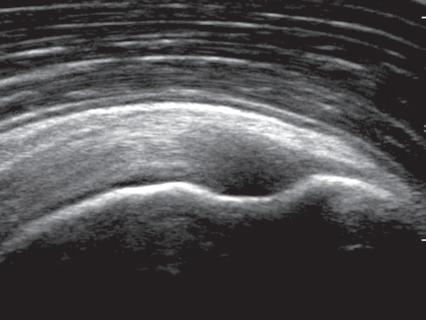

Musculoskeletal structures have characteristic appearances on ultrasound imaging.2 Normal tendons appear hyperechoic with a fiber-like or fibrillar echotexture (see Fig. 1.4).3 At close inspection, the linear fibrillar echoes within a tendon represent the endotendineum septa, which contain connective tissue, elastic fibers, nerve endings, blood, and lymph vessels.3 Continuous tendon fibers are best appreciated when they are imaged long axis to the tendon. On such a long axis image, by convention the proximal aspect is on the left side of the image, with the distal aspect on the right. In short axis, normal hyperechoic tendon fibers appear as bristles of a brush seen on end (see Fig. 1.9A). Normal muscle tissue appears relatively hypoechoic (Fig. 1.6). At closer inspection, the hypoechoic muscle tissue is separated by fine hyperechoic fibroadipose septa or perimysium, which surrounds the hypoechoic muscle bundles. The surface of bone or calcification is typically very hyperechoic, with posterior acoustic shadowing and possibly posterior reverberation if the surface of the bone is smooth and flat (Fig. 1.6). The hyaline cartilage covering the articular surface of bone is hypoechoic and uniform (Fig. 1.7A and B), whereas the fibrocartilage, such as the

FIGURE 1.7 Cartilage. A, Ultrasound image transverse over the distal anterior femur shows hypoechoic hyaline cartilage (arrowheads) F, Femur. B, Ultrasound image of infraspinatus in long axis (I) shows a hyperechoic fibrocartilage glenoid labrum (arrowheads) and hypoechoic hyaline cartilage (curved arrow). Note hyperechoic epidermis and dermis (E/D), and adjacent deeper hypoechoic hypodermis with hyperechoic septa. G, Glenoid; H, humerus.